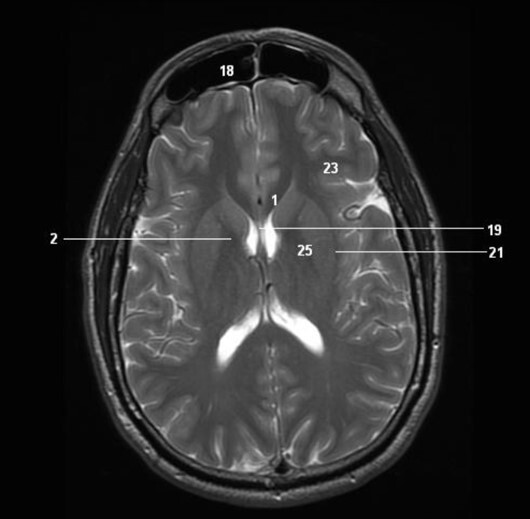

12

Q

Label 2,18,19,21

A

2=Rt internal capsule

18=Frontal sinus

19=Septum pellucidum

21=Lt external capsule

13

Label 3,5,7,10,11,12,14,20

3=Lt frontal lobe

5=Lt Lentiform nucleus

7=Lt internal capsule

10=Insula

11=Lt Claustrum

12=Rt Thalamus

14=Splenium, CC

20=Lt Interventricular foramen